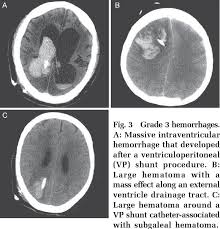

Pdf Hemorrhage Rates Associated With Two Methods Of Ventriculostomy External Ventricular Drainage Vs Ventriculoperitoneal Shunt Procedure Semantic Scholar

Pdf Intraventricular Hemorrhage A Catastrophic Complication After Removal Of Old Ventriculoperitoneal Shunt